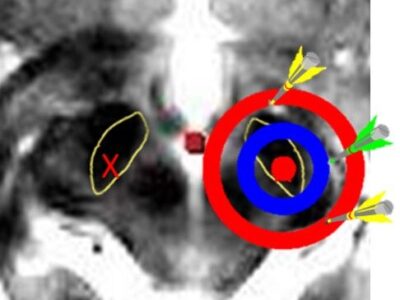

Welcome to this e-learning resource for stereotactic functional neurosurgery and DBS, with focus on visual anatomical targeting.

The aim of this website is to cover every detail of DBS that is of importance from a clinical perspective, including the most fundamental basics. The site is therefore suitable for young colleagues who are starting their training within the field of stereotactic functional neurosurgery and DBS. Hopefully, some of the lectures will also be of value to more experienced colleagues, and to nonneurosurgeons with an interest in DBS.